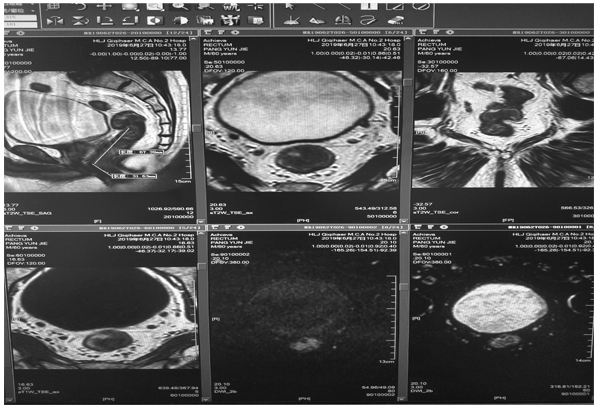

直肠高分辨磁共振多参数成像